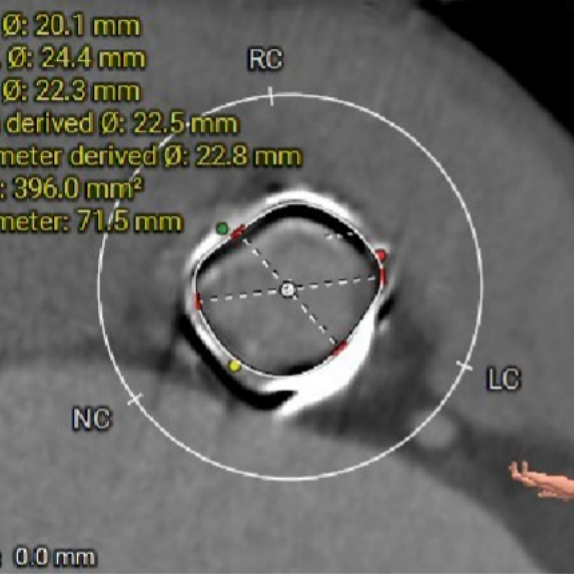

术前CT评估-TAVI viv

Annulus——内径

Annulus——外径

选瓣依据:该主动瓣原置换生物瓣为Hancoke II#25,CT测量生物瓣瓣环周长折算直径约22.8mm,瓣架高度约18.0mm;